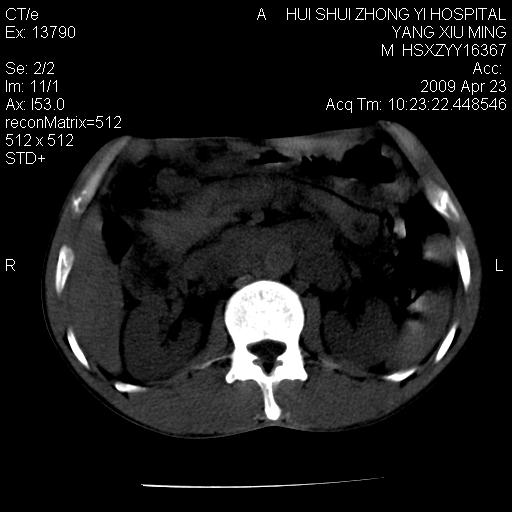

上腹部疼痛一月,呕吐10天,发现左侧颈部包快10天 胸部cr片未见明显异常。

腹膜后淋巴结增大,转移、淋巴瘤?胰腺增大,胰腺炎?占位?颈部考虑增大淋巴结。建议腹部增强扫描。

连最基本的ct值都没有测        腹部的窗宽窗位太大了     影响诊断

黑!广泛淋巴结肿大不符合胰腺癌转移。胰腺周围淋巴结肿大致使胰腺看起来大。考虑淋巴瘤可能大。